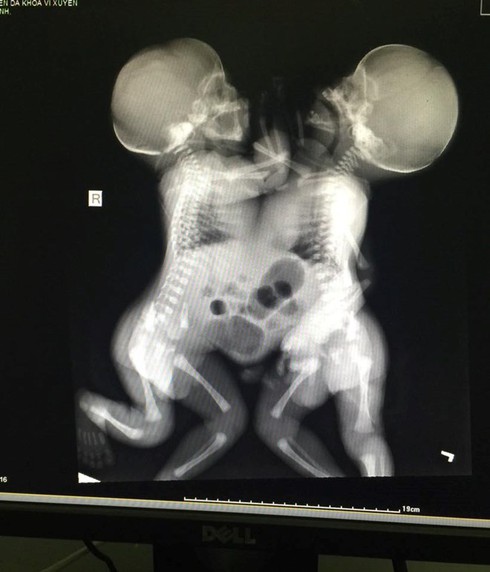

Sau khi được chuyển từ Bệnh viện Đa khoa huyện Vị Xuyên (Hà Giang) xuống Bệnh viện Việt Đức vào tối 14-7 để chờ phẫu thuật tách rời, hiện sức khỏe của cặp song sinh dính liền nhau từ ngực đến bụng, chung dây rốn (con sản phụ Phàn Thị Chẩy, 20 tuổi, ở huyện Vị Xuyên, Hà Giang - Báo ANTĐ đã đưa tin) diễn biến xấu, tiên lượng rất dè dặt.

Theo thông tin từ Bệnh viện Việt Đức, cặp song sinh này đang được chăm sóc và điều trị tại Khoa Hồi sức cấp cứu của bệnh viện. Sau khi hội chẩn, bệnh viện nhận định tim và gan, xương ức của 2 trẻ song sinh là một khối dính liền nên việc phẫu thuật tách rời gần như không thể thực hiện được, kể cả phương án cứu 1 trong 2 đứa trẻ cũng đã được tính đến. Hiện cặp song sinh đang được thở máy, nuôi dưỡng theo đường tĩnh mạch và đường ruột.